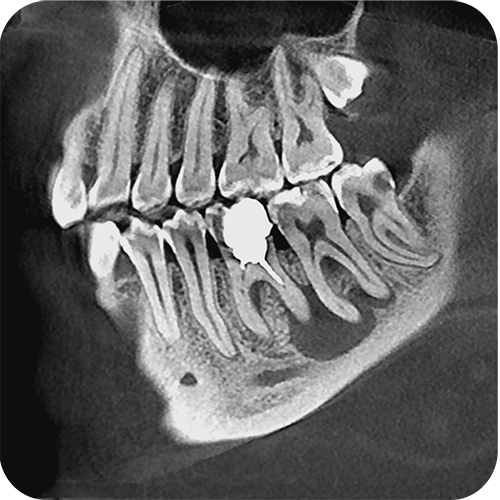

- Плоскопанельный детектор имеет самую высокую в классе разрешающую способность